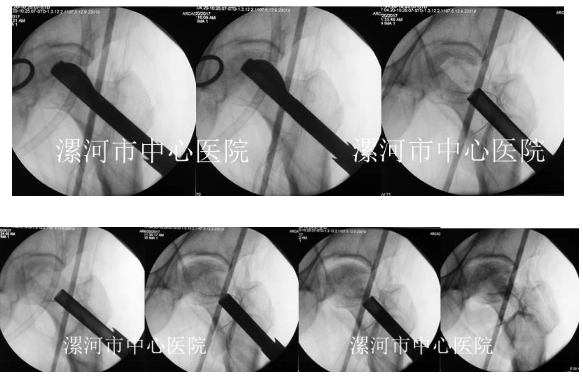

(二)开展了基于术中CT扫描结果微创治疗胸腰椎骨折技术

国内首次提出基于术中CT扫描精准、微创治疗胸腰椎骨折。

国内首家提出新理念,在COA、国际骨科会议上报道,得到国内专家的认可。

论文发表在中华医学杂志。